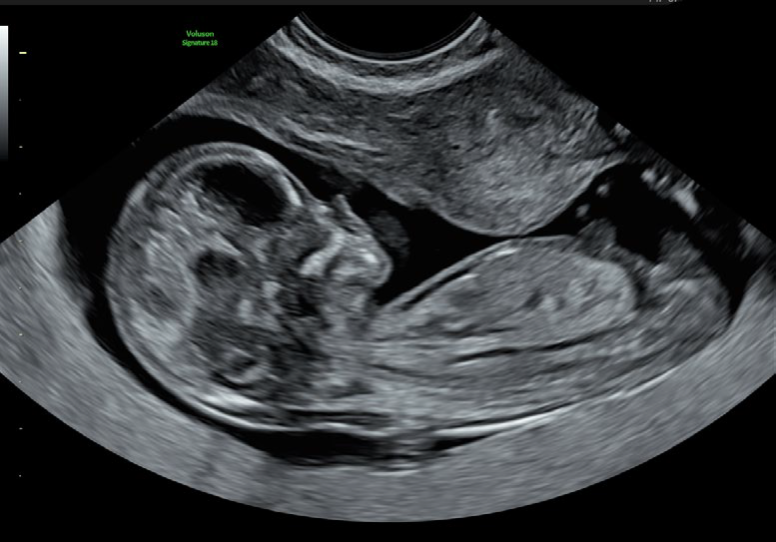

El Voluson Signature 18 se basa en un nuevo motor de imágenes: la arquitectura Voluson Unity, que ofrece velocidades de procesamiento y velocidades de fotogramas más rápidas que nuestros sistemas Signature anteriores. Este hardware y software son la base del sistema y sientan las bases para las capacidades actuales y futuras. Experimente ahora un nuevo nivel de profundidad y claridad.

Procesamiento rápido de volumen 3D/4D